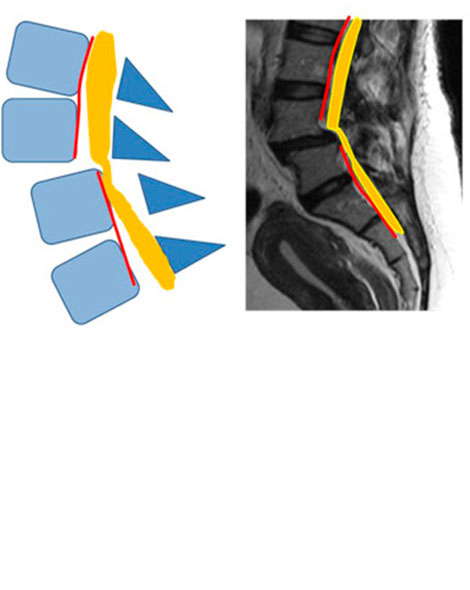

Es cuando se produce que una vértebra se desliza hacia delante, fuera de su lugar normal, sobre la vértebra que se encuentra debajo de ella.

TIPOS

2.- ÍSTMICAS